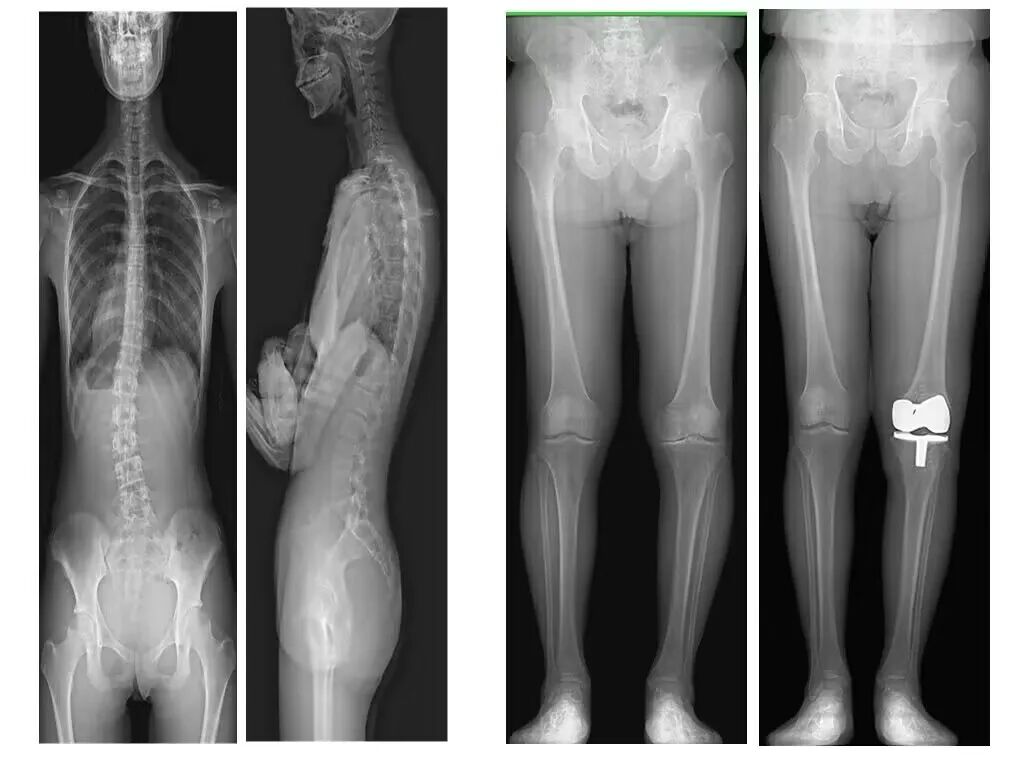

骨科:

高清晰度骨骼成像、关节成像、长轴成像(整体愈合后的判断);